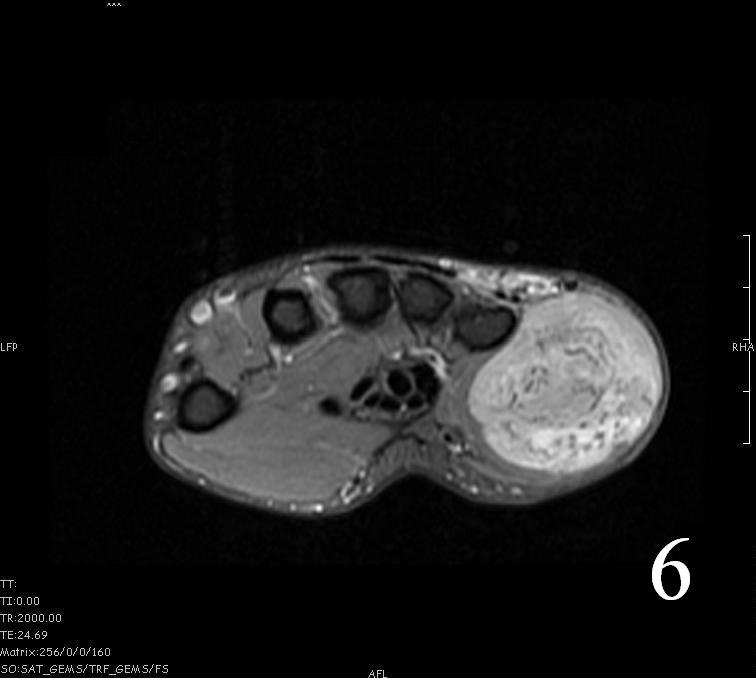

MRI

- Hyperintense signal on T2, sometimes low to intermediate signal on T2 if there is extensive fibrous tissue within the tumor (Fig. 6, Fig. 9).

- Possible extensive hypercellular fibrous tissue and hemosiderin seen on T2

Fig. 4-9: MRI of a rhabdomyosarcoma of the hand. The MRI is nonspecific and shows a heterogeneous mass particularly on postgadolinium images T1 W images (Fig. 8) and T2 W images (Fig. 9).